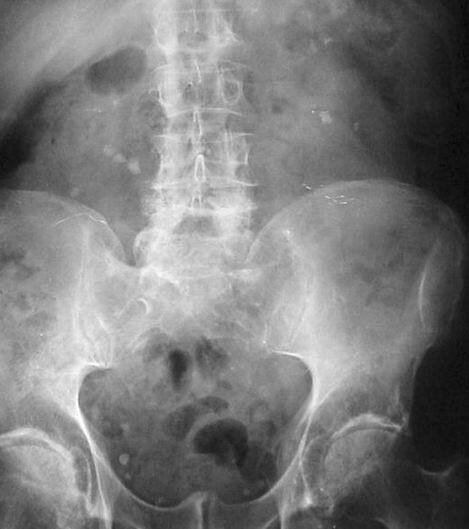

ऑपरेशन से पहले डॉक्टर्स ने इस महिला की दो एमआरआई रिपोर्ट तक चैक नहीं की जिसमें साफ जाहिर था कि महिला की पेल्विक किडनी है वो भी हेल्दी. फोटोः गूगल फ्री इमेज

दरअसल, डॉक्टर्स ने गलती से महिला की हेल्दी किडनी को शरीर में बढ़ने वाला एक कैंसरनुमा ऑर्गन समझा जिसे ऑपरेशन के दौरान निकाल दिया गया. जानिए क्या था पूरा मामला. फोटोः गूगल फ्री इमेज

ऑपरेशन से पहले डॉक्टर्स ने जांचा कि महिला के पेल्विक में कोई मांस जमा है जिसे उन्होंने कैंसर का नाम दे दिया और महिला का इमरजेंसी में ऑपरेशन कर दिया. ऑपरेशन में इस मांस यानि पेल्विक किडनी को निकाल दिया गया. फोटोः गूगल फ्री इमेज